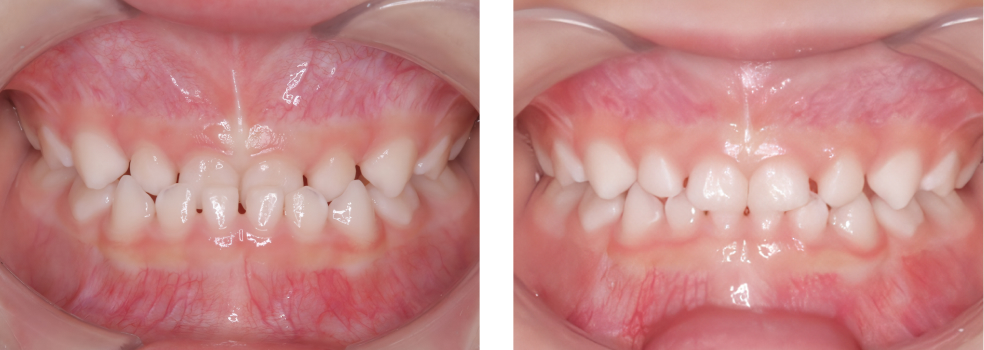

小児歯科

術前

術後

| 治療内容 | 外傷による歯冠破折に対してCRにて破折片の再接着を行った |

|---|---|

| 治療期間・回数 | 1日・1回 |

| 費用 | 保険適用となります |